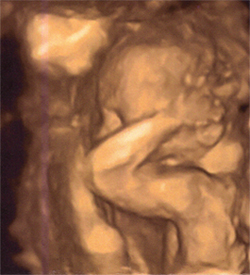

Screenshot 3 of 4 from Album:

Family

baby2

That's pretty damn incredible. Have a baby on the way? Congrats!